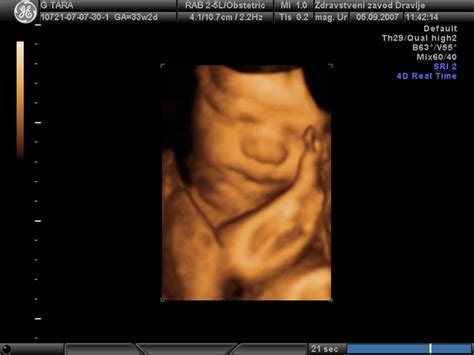

Ultrazvočni pregled z merjenjem nuhalne svetline (NS) je eden izmed najpomembnejših pregledov v zgodnji nosečnosti, priporočljiv za vse nosečnice. Opravlja se med 11. in 14. tednom nosečnosti. Med tem pregledom ginekolog z ultrazvokom izmeri debelino tekočine pod kožo v zatilnem delu ploda, imenovano nuhalna svetlina. Povečana nuhalna svetlina lahko nakazuje na povečano tveganje za kromosomske napake, kot sta Downov sindrom, Edwardsov sindrom ali Patauov sindrom. Kljub temu je pomembno razumeti, da gre za presejalni test, ki ne postavlja diagnoze, temveč le oceni verjetnost za določene nepravilnosti. Zmožnost tega testa za odkrivanje plodov z Downovim sindromom je približno 75-80 %.